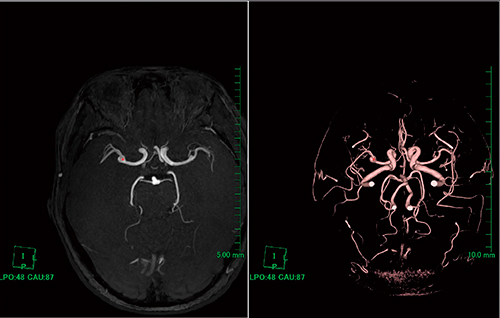

(3)左ウインドウのMIPを動脈瘤が見えるスライスに合わせる(図4)。

図4 スライス位置合わせ